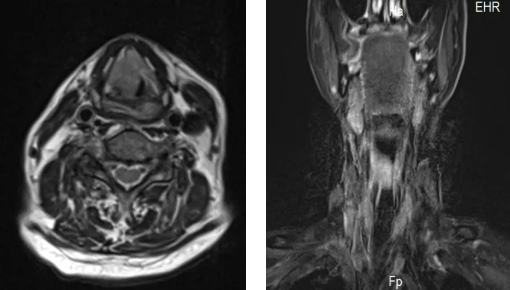

84歲的趙大爺因喉部腫瘤,三個(gè)月前做了氣道改造手術(shù),平時(shí)靠一根氣管套管輔助呼吸。沒想到一天深夜,這根“生命管”突然脫落,頸部的人工氣道口也很快閉合。老人呼吸困難,被家人緊急送往隨州市中心醫(yī)院。

情況萬分危急,趙大爺呼吸急促,只能坐著喘氣,臉色因缺氧逐漸發(fā)青。耳鼻咽喉頭頸外科主任蔡奇山接到通知后火速趕到。檢查發(fā)現(xiàn),原先的呼吸通道已經(jīng)堵閉,必須立即手術(shù)重建氣道。

時(shí)間就是生命。在征得家屬同意后,凌晨的手術(shù)室里展開了一場(chǎng)生命接力。蔡奇山帶領(lǐng)團(tuán)隊(duì)緊急為趙大爺進(jìn)行了喉部腫瘤切除和永久性氣道重建手術(shù)。經(jīng)過四個(gè)多小時(shí)的全力搶救,手術(shù)順利完成。趙大爺?shù)暮粑匦马槙?,脫離了生命危險(xiǎn)。在重癥監(jiān)護(hù)室觀察穩(wěn)定后,他已轉(zhuǎn)回耳鼻咽喉頭頸外科病房繼續(xù)康復(fù)治療,目前恢復(fù)情況良好。